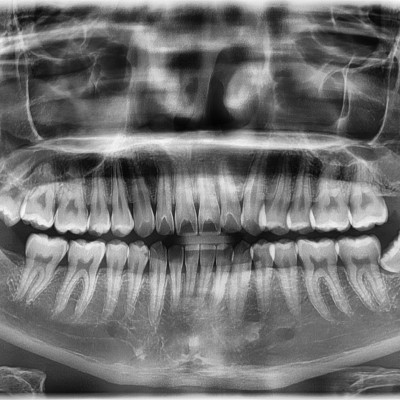

#18,38,48 사랑니 발치 #18,38,48 사랑니 발치 구강 외과 전문의가 당일 발치했습니다. -----------------------..

작성자 이턱이 작성일 03-12 조회 22